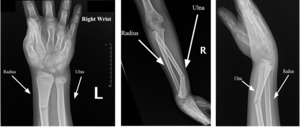

Comminuted Displaced And Angulated Distal Radial And Ulnar Distal radius fractures are the most common orthopaedic injury and generally result from fall on an outstretched hand. The authors present the case of a six year old boy with a fractured right distal radius and ulna, causing mildly comminuted displaced angulated fractures of the right distal radial and ulnar metaphyses.

Comminuted Displaced And Angulated Distal Radial And Ulnar It is important to classify the type of fracture because intra articular fractures, open fractures, comminuted fractures, and displaced fractures (when the broken pieces of bone do not line up straight) are more difficult to treat than other types of fractures. A randomized, controlled trial of distal radius fractures with metaphyseal displacement but without joint incongruity: closed reduction and casting versus closed reduction, spanning external fixation, and optional percutaneous k wires. Comminuted, dorsally angulated distal radial fracture with associated ulnar styloid fracture but without involvement of the radiocarpal or distal radioulnar joints. Surgical treatment of fractures of the distal radius is indicated when these fractures are largely displaced, reduced but unstable, irreducible, comminuted, or involving the distal radio ulnar joint or radiocarpal joint.